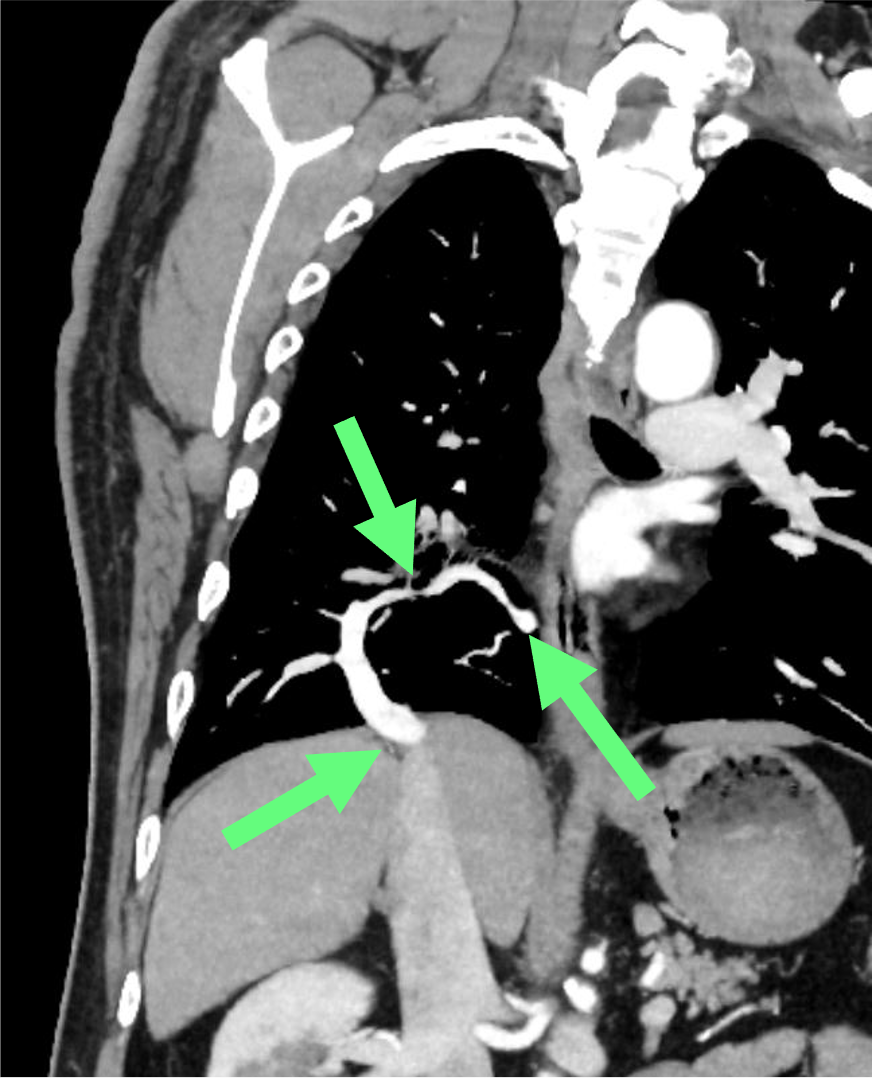

図1.造影CT(動脈相)冠状断MIP像

右肺下葉の肺静脈は、大部分が合流しながら下方へscimitar状に走行している(矢印)。